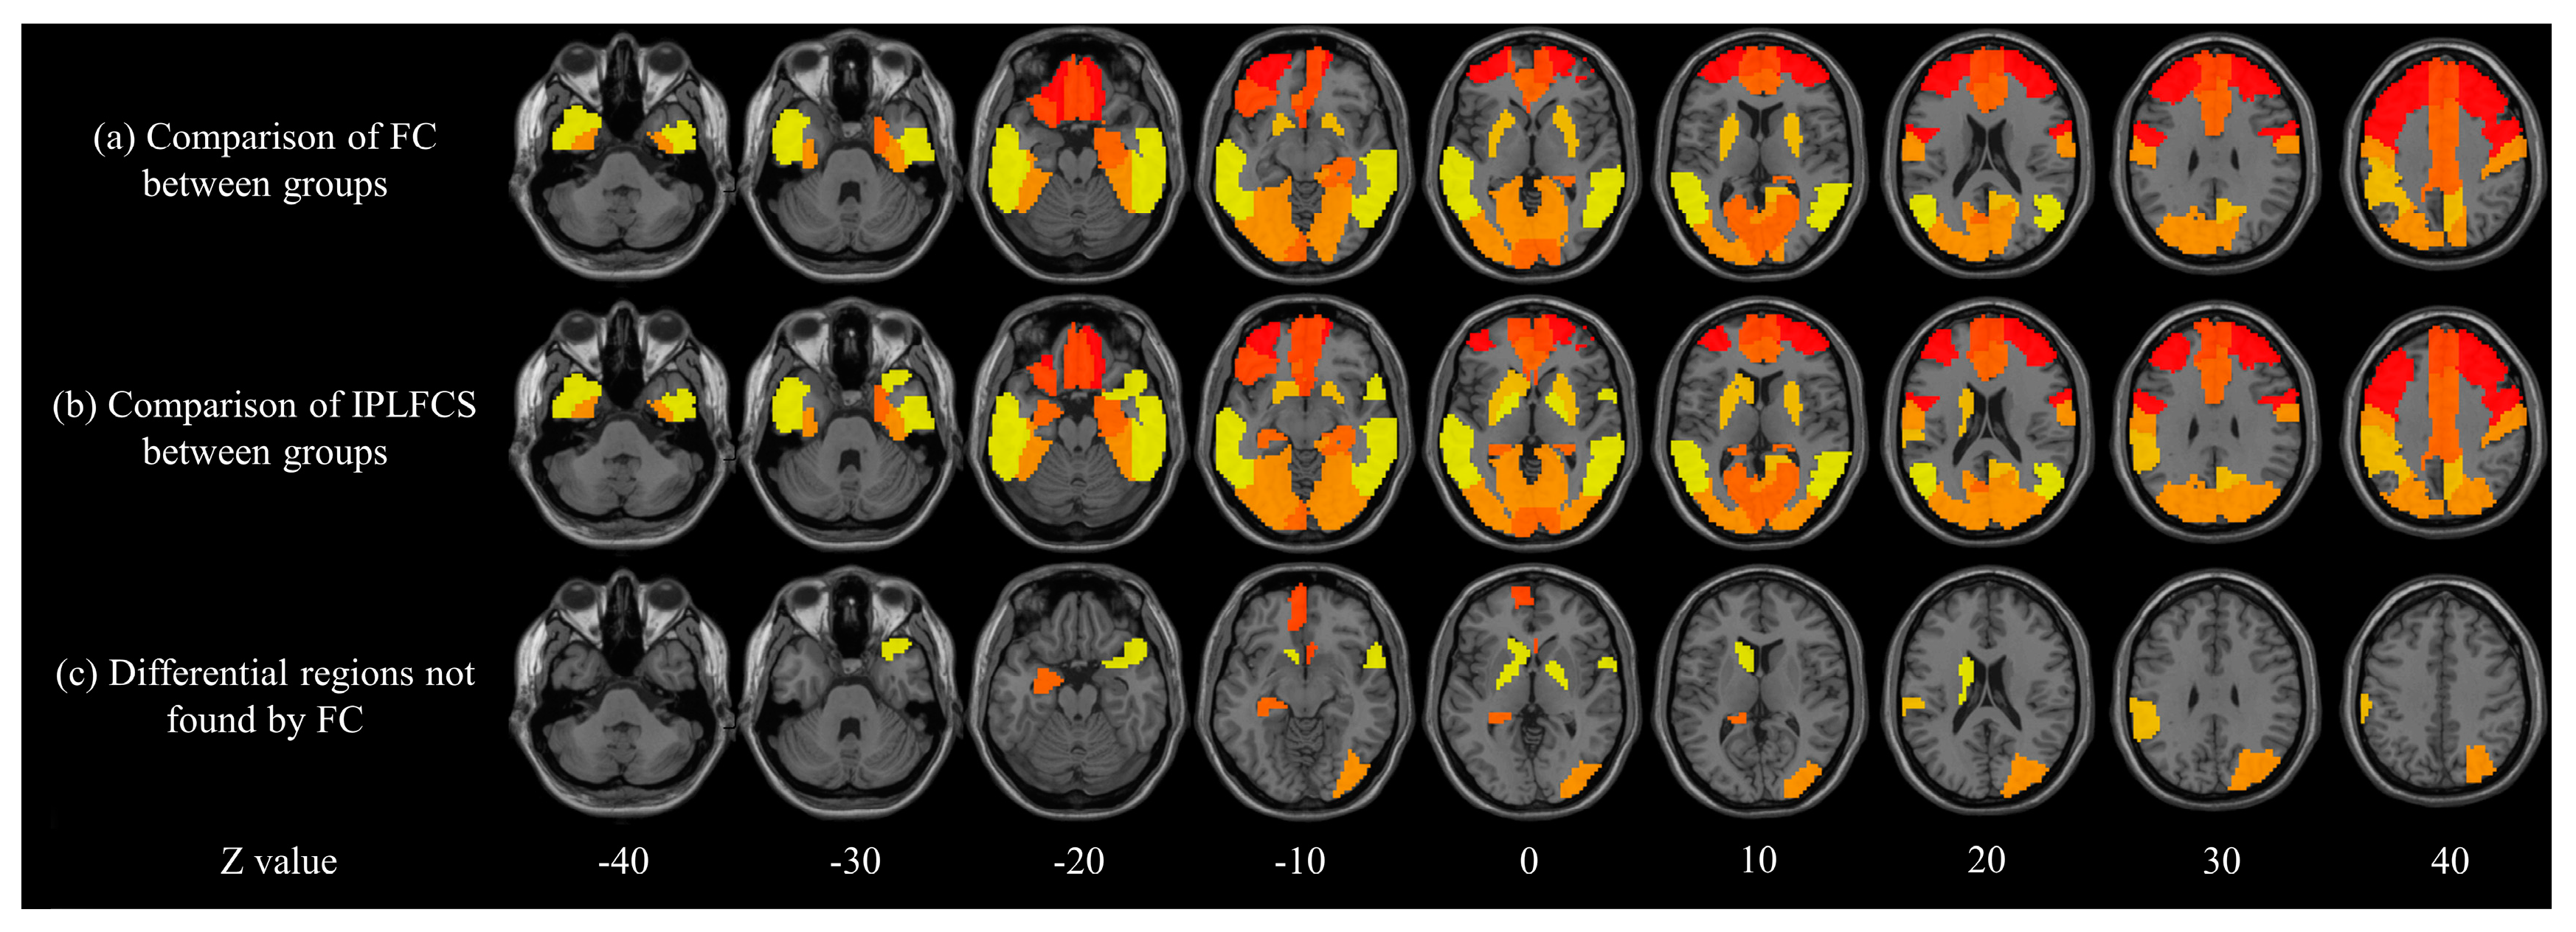

Figure 2 shows that the IPLFCS could identify more different brain regions in the between-group comparison of NC and SCD. Figure 2a,b show the between-group comparison of FC and IPLFCS, respectively, at the level of the brain regions. Figure 2c shows that the IPLFCS found more differential brain regions, which include the olfactory cortex, superior frontal gyrus, hippocampus, amygdala, lenticular nucleus, occipital gyrus, supramarginal gyrus, caudate nucleus, and temporal gyrus.

Figure 2. Group comparison between NC and SCD in brain regions. (a) Comparison of FC between group; (b) Comparison of IPLFCs between group; (c) Differential brain regions were found by the between-group comparison of IPLFCS but not in the between-group comparison of FC. Z value represents the z-axis of standard space. Differential brain regions found: amygdala and temporal gyrus (see Z = −20), hippocampus and olfactory (see Z = −10), superior frontal gyrus and lenticular nucleus (see Z = 0), caudate nucleus (see Z = 10), occipital gyrus (see Z = 20), and supramarginal gyrus (see Z = 30).